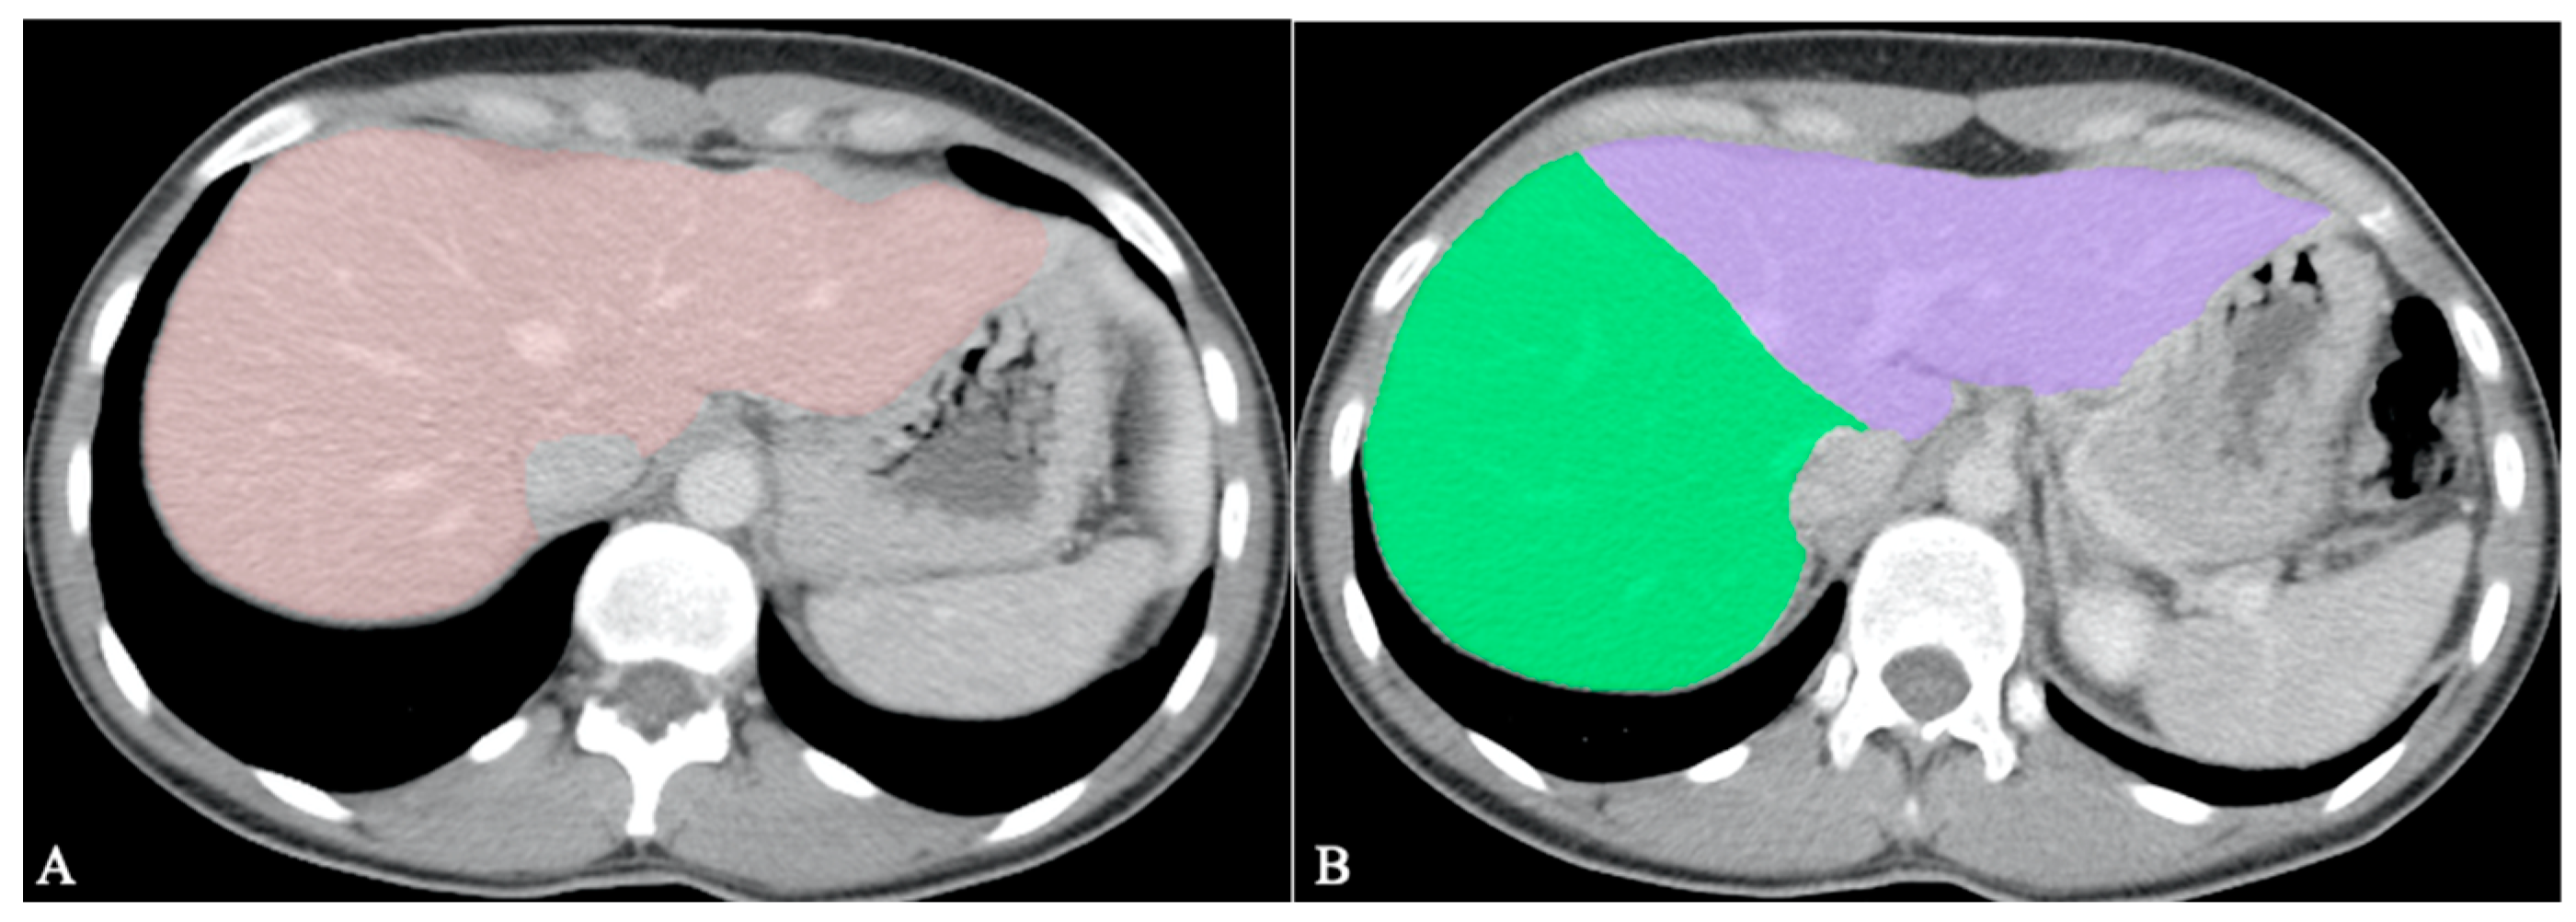

- Jimenez-Pastor, A.; Alberich-Bayarri, A.; Lopez-Gonzalez, R.; Marti-Aguado, D.; França, M.; Bachmann RS, M.; Marti-Bonmati, L. Precise whole liver automatic segmentation and quantification of PDFF and R2* on MR images. European radiology 2021, 31, 7876–7887. [Google Scholar] [CrossRef]

| Jimenez-Pastor et al. [69] | 2021 | Liver segmentation, fat and iron quantification | MRI | DL | 93% |

| Bousabarah et al. [70] | 2021 | Liver and HCC segmentation | MRI | DL | 91% for liver 68% for HCC |